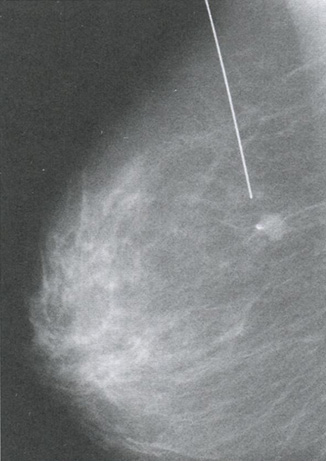

- применение контролируемой пункции патологических солидных образований, позволяющей получить материал для цитологического, гистологического и иммуногистохимического исследований (рис. 3.4);

Рис. 3.4. Пункция патологического солидного образования